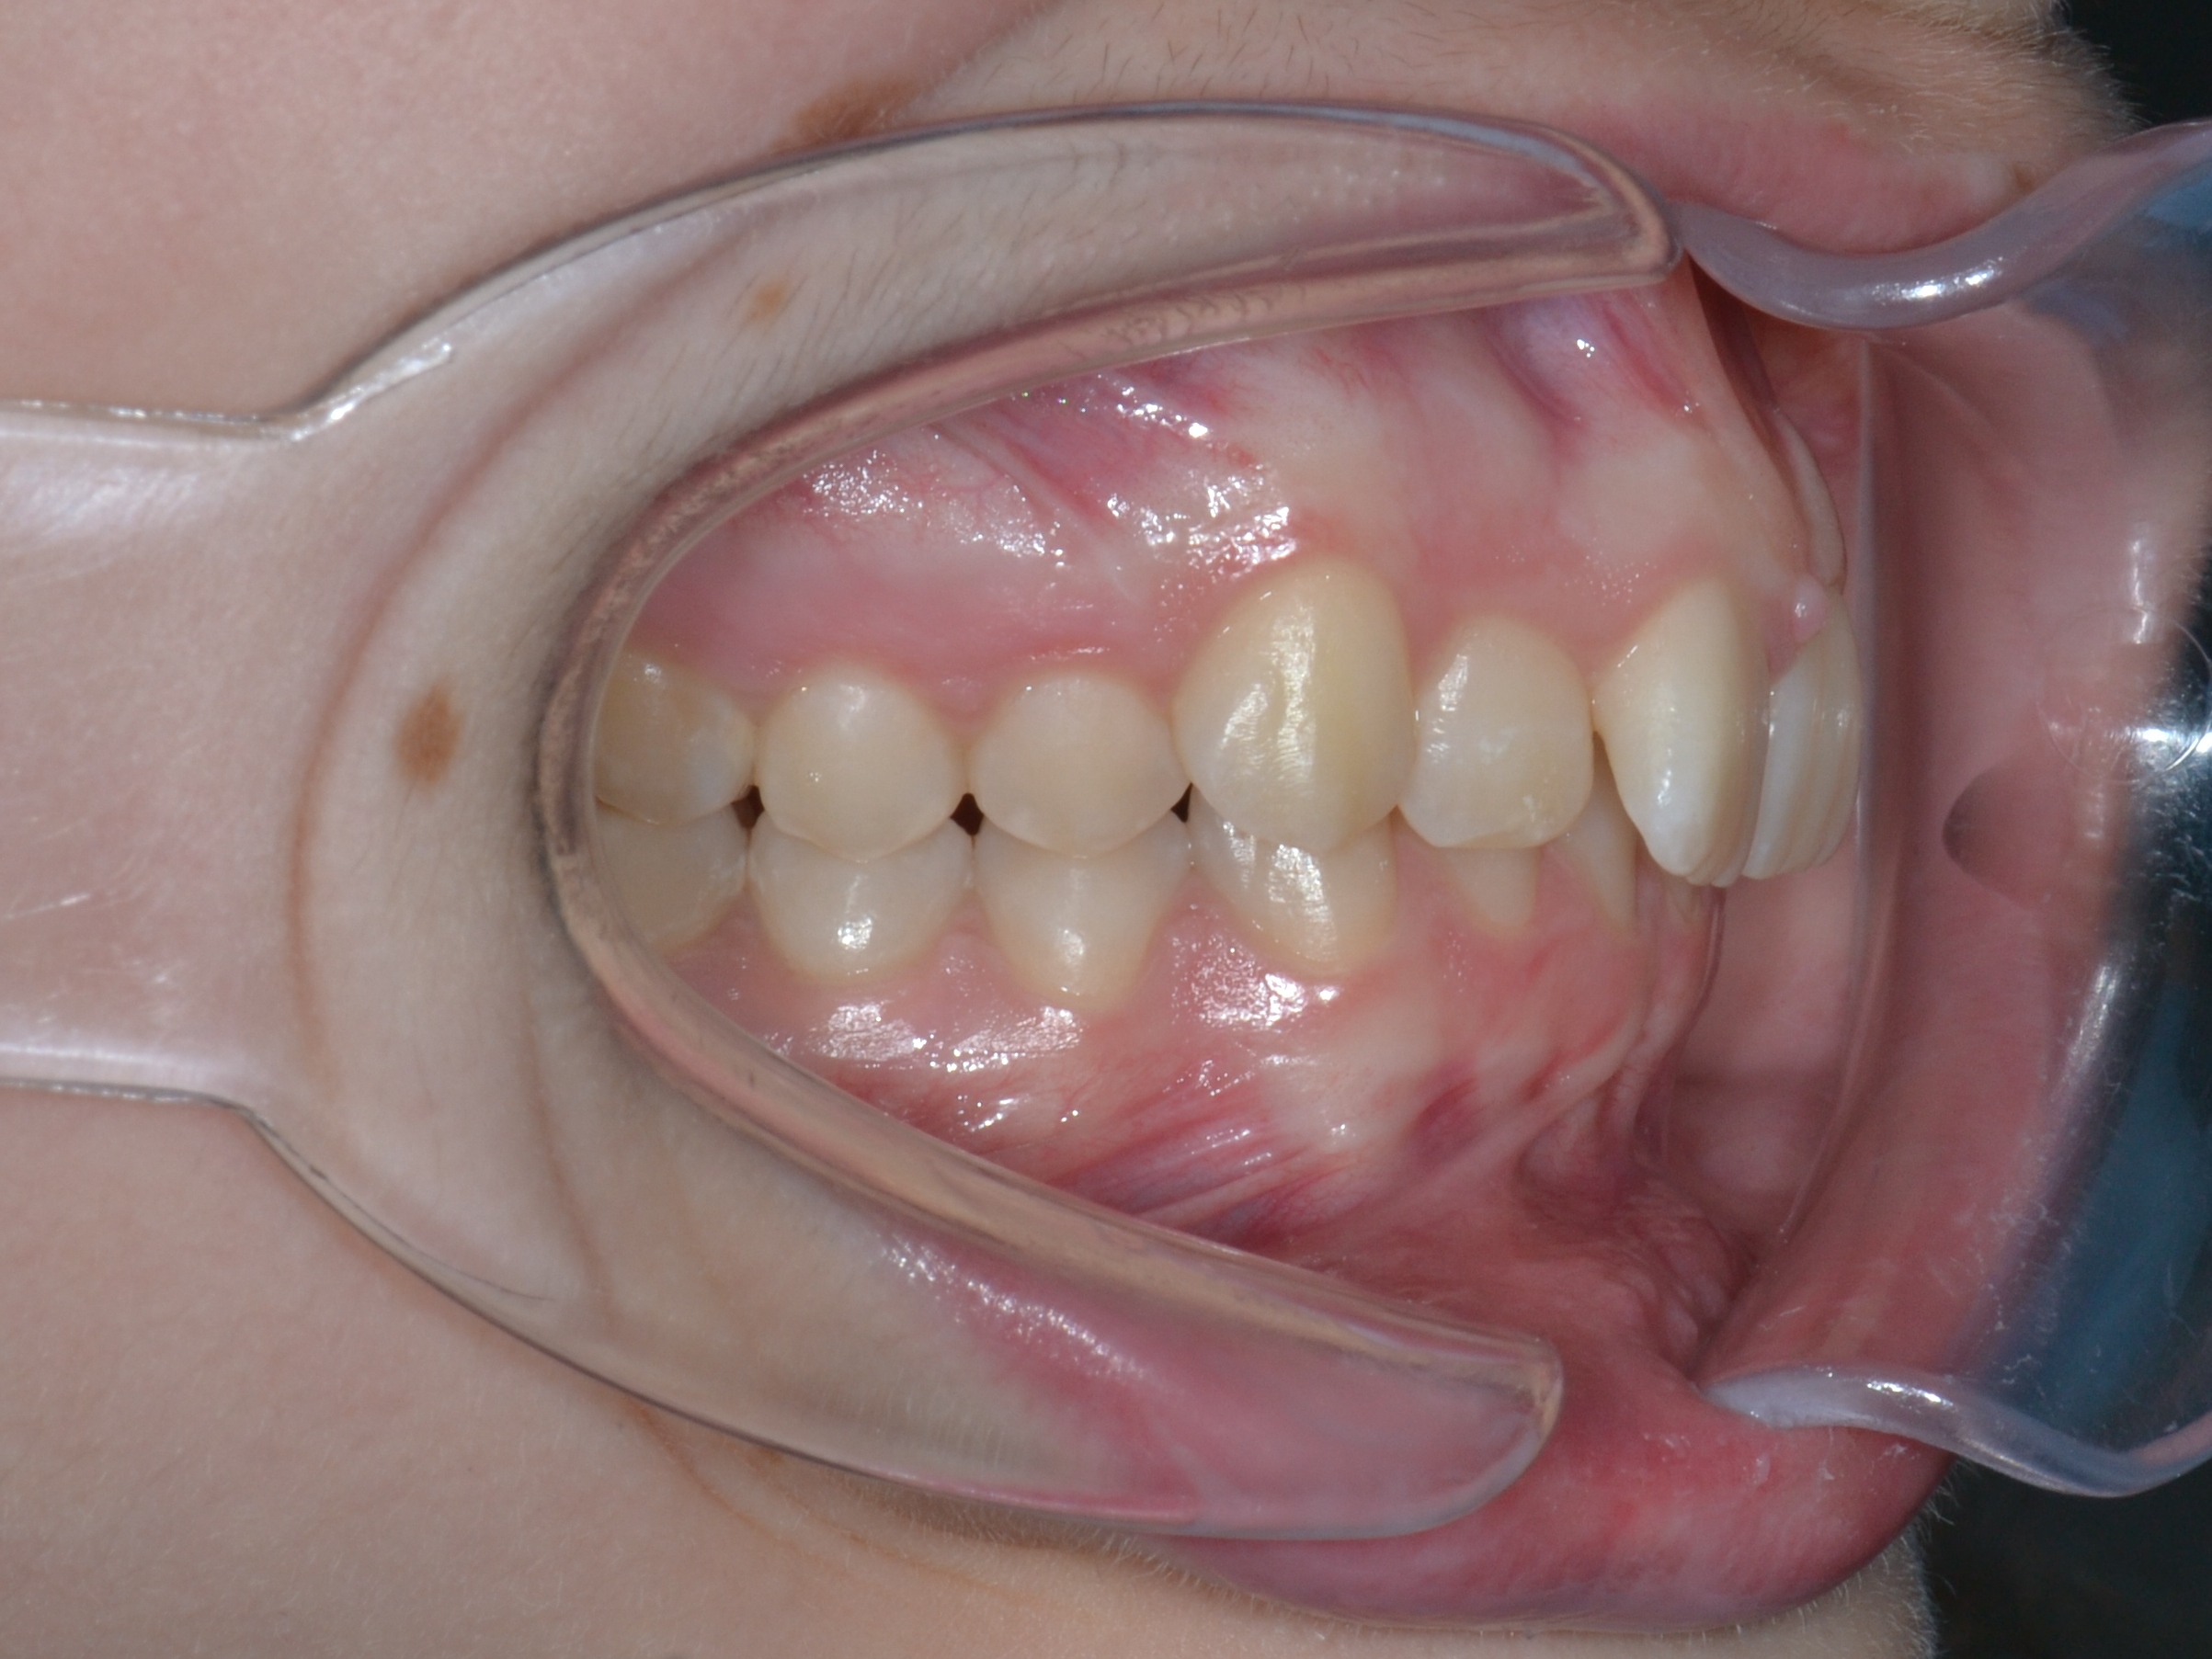

Выявленные проблемы

• Глубокое резцовое перекрытие

• Сужение верхнего и нижнего зубных рядов

• 23 зуб в щёчном положении, 22 зуб в нёбном положении с дефицитом места

• Скученное положение зубов дистальное положение и ротация нижней челюсти

• Патологическая стираемость и генерализованный пародонтит с рецессией десневого края

Брекет-система Q